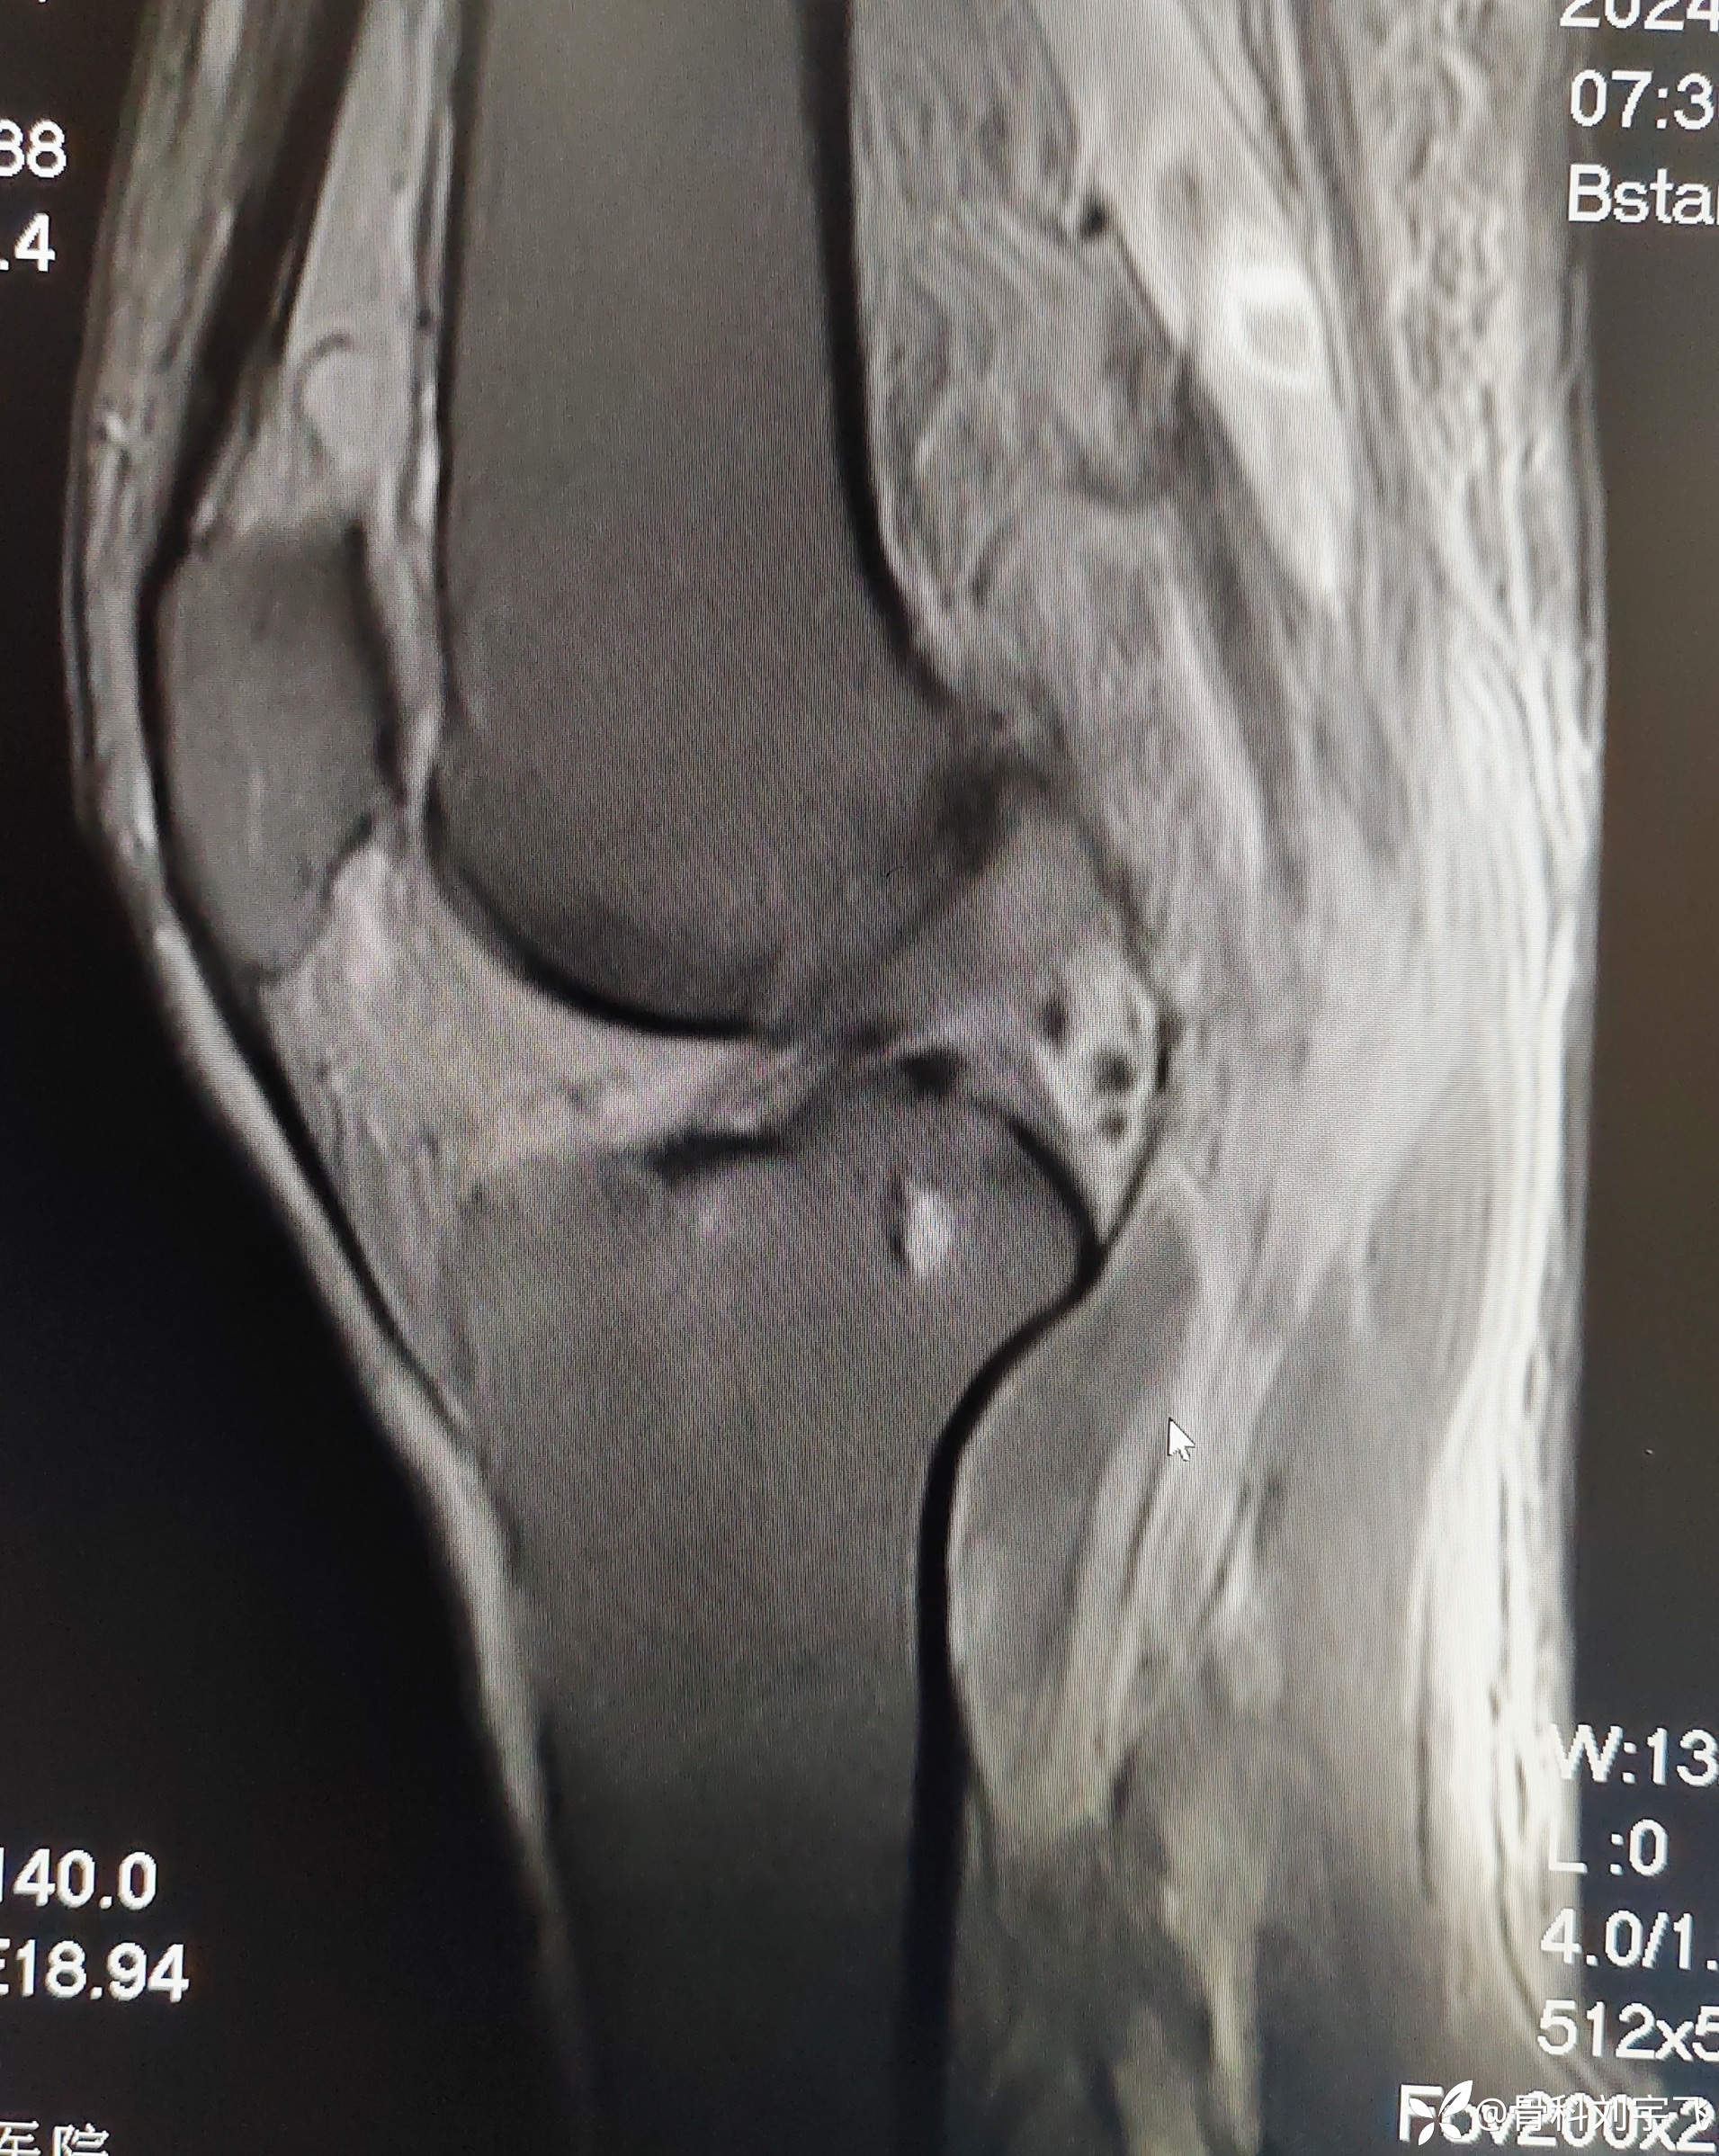

无诱因膝关节疼痛、肿胀做了MRI诊断关节退变、半月板撕裂,最后病因是下肢血栓?

临床诊断:内侧半月板撕裂 肌间软组织水肿?

辅助检查:MRI